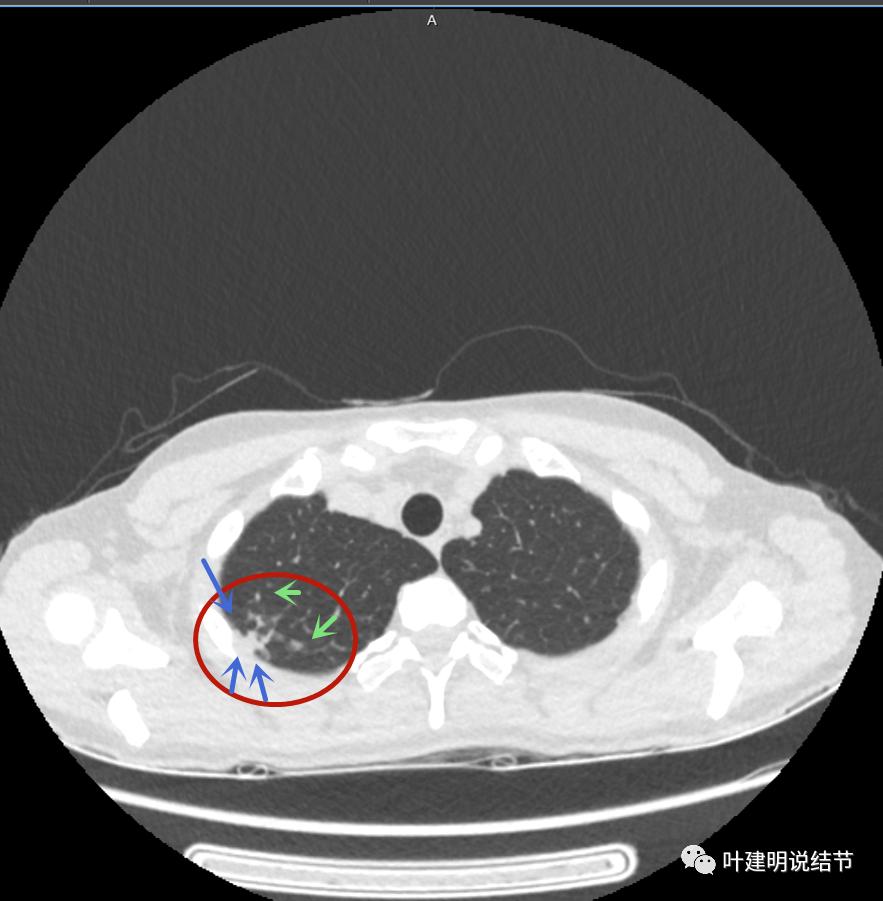

有卫星灶(绿色箭头),邻近胸膜明显增厚,且模糊,边不清

邻近胸膜增厚

主病灶此层面似三角形,邻近胸膜增厚(蓝色箭头),结节实性部分密度较高(粉色箭头),边缘显模糊(砖色箭头)

上图与恶性较为符合,空洞性病灶,壁厚薄不均,增厚部分还凹凸不平(细红色箭头所指)

上图磨玻璃部分密度过低,且与正常肺组织界限模糊(砖色箭头),粉色箭头示囊壁密度过高的点状,蓝色箭头示邻近胸膜处的增厚

上图也像恶性,但整个囊壁的密度感觉过高了点,边缘磨玻璃淡、散且模糊,邻近胸膜有增厚

上图病灶的边相对比较光,没有毛刺征,邻近胸膜增厚

上图病灶边缘比较平直,没有膨胀性(桔色箭头),旁边的磨玻璃影淡且界限不清,邻近胸膜增厚。